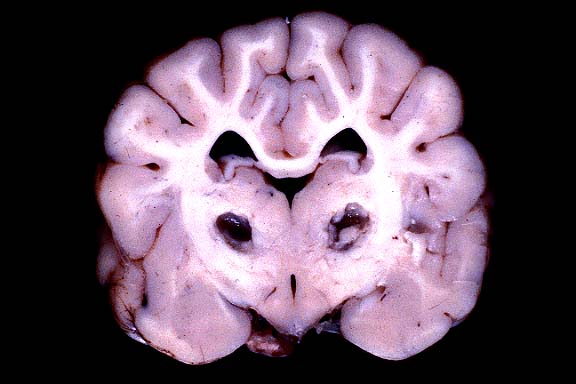

- Gross Pathology: Bilaterally symmetrical, 5 x 3 mm

areas of malacia were present in the thalamus (see photograph).

Multifocal areas in ventral portions of the cerebellum had thin

- Case 11-4. Cerebrum. (see description above)

of brain scans. The distribution of the malacic "butterfly"

lesions is characteristic. The biochemical basis for the disease

in these dogs is unknown. The owners were not aware of other

- 1. Thalamus: Cavitation and necrosis, focally extensive,

with gitter cells and mild gliosis, Alaskan Husky, canine.

2. Cerebral cortex: Necrosis, laminar, focally extensive, with

mild to moderate gliosis.

3. Cerebellum: Purkinje and granular cell loss, multifocal, segmental,

with moderate gliosis.